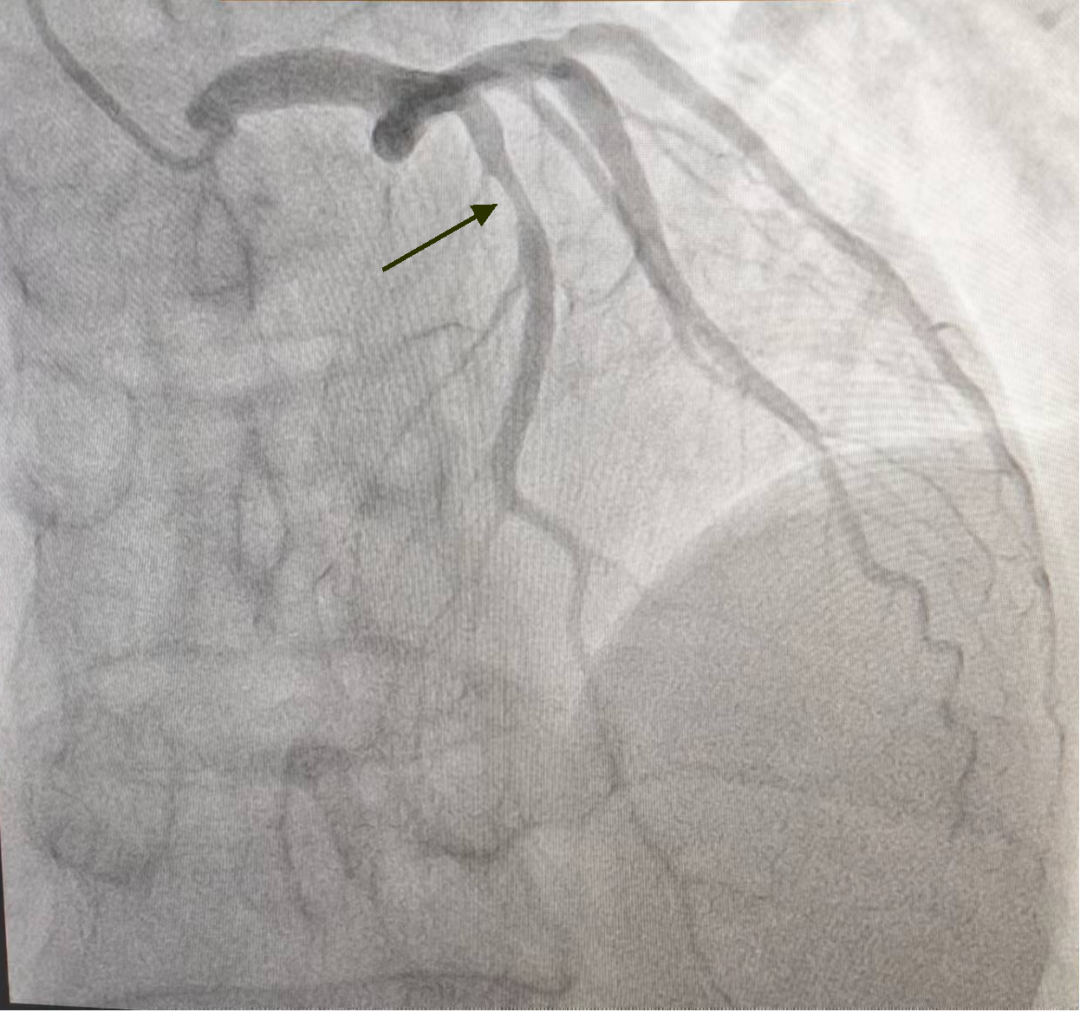

张院长看过病人后,迅速做出判断,并给出诊治方案:患者均为中老年男性,此次急性发病,均明确诊断为急性ST段抬高型心肌梗死,根据最新《急性ST段抬高心肌梗死诊断与治疗指南》,需尽早开通梗死相关血管,恢复心肌再灌注,两位患者发病均在6小时内,可选择静脉溶栓与急诊PCI术。与患者家属积极沟通,分别首先给予静脉溶栓治疗,均判定溶栓再通,溶栓后行冠脉造影提示病例1患者前降支近中段残余狭窄约70%,无需干预,规范药物治疗;病例2患者右冠脉“罪犯”血管残余狭窄80-90%,于右冠脉植入支架1枚,术后患者症状缓解,生命体征平稳,安全返回心内科重症监护室。